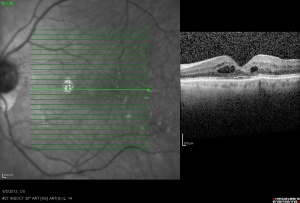

Optical Coherence Tomography (OCT) objectively obtains cross-sectional, high-resolution images of the retina. In CME, OCT can be diagnostic through measurement of retinal thickening with depiction of the intraretinal cystic areas of low reflectivity in OPL (Image 4)[32][33] and depiction of the mechanical forces induced by vitreomacular interface abnormalities (such as VMT or epiretinal membrane (ERM)) via a hyperreflective band on the inner surface of the retina.[34][35] In severe CME, subfoveal fluid may be evident on OCT.